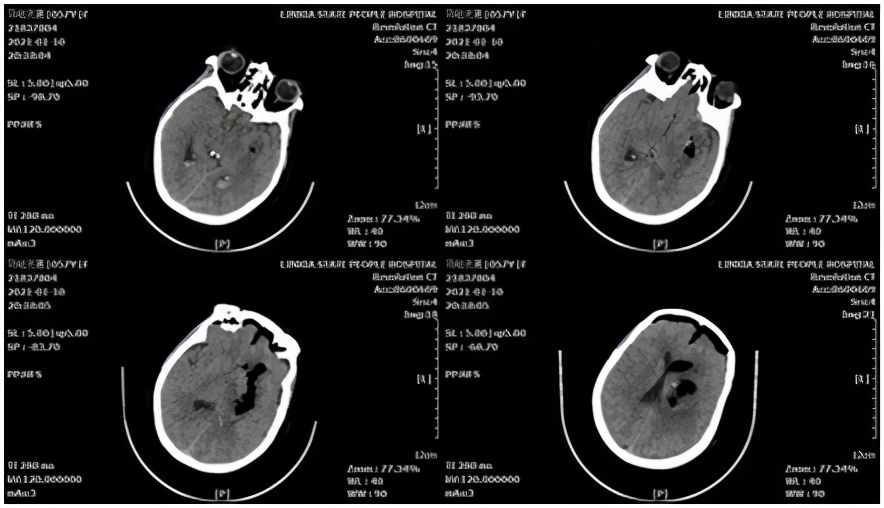

术中采用额中回入路,并用血肿-脑脊液置换技术,最终清除基底节区、脑室内全部血肿,术后血肿腔不放置引流管,取得了良好效果。

术后头颅CT